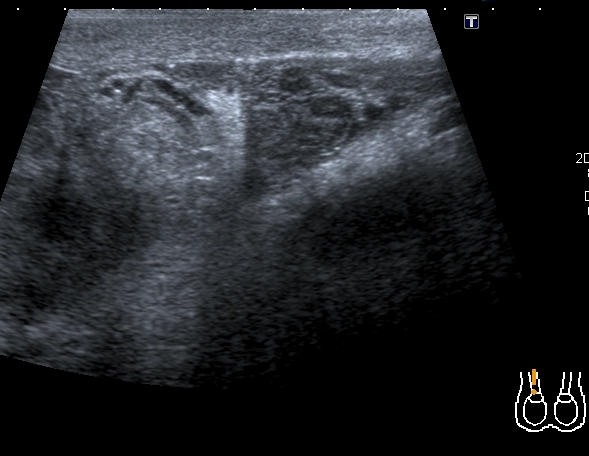

В приёмный покой больницы поступил мальчик 14 лет с жалобами на отёк правой половины мошонки и боли в правом яичке. При УЗИ - правое яичко увеличено отностиельно левого, изменено по структуре, расположено выше левого.

На энергетическом доплере - обогащён кровоток в отёчном придатке и семенном канатике, в яичке кровоток не дифференцируется